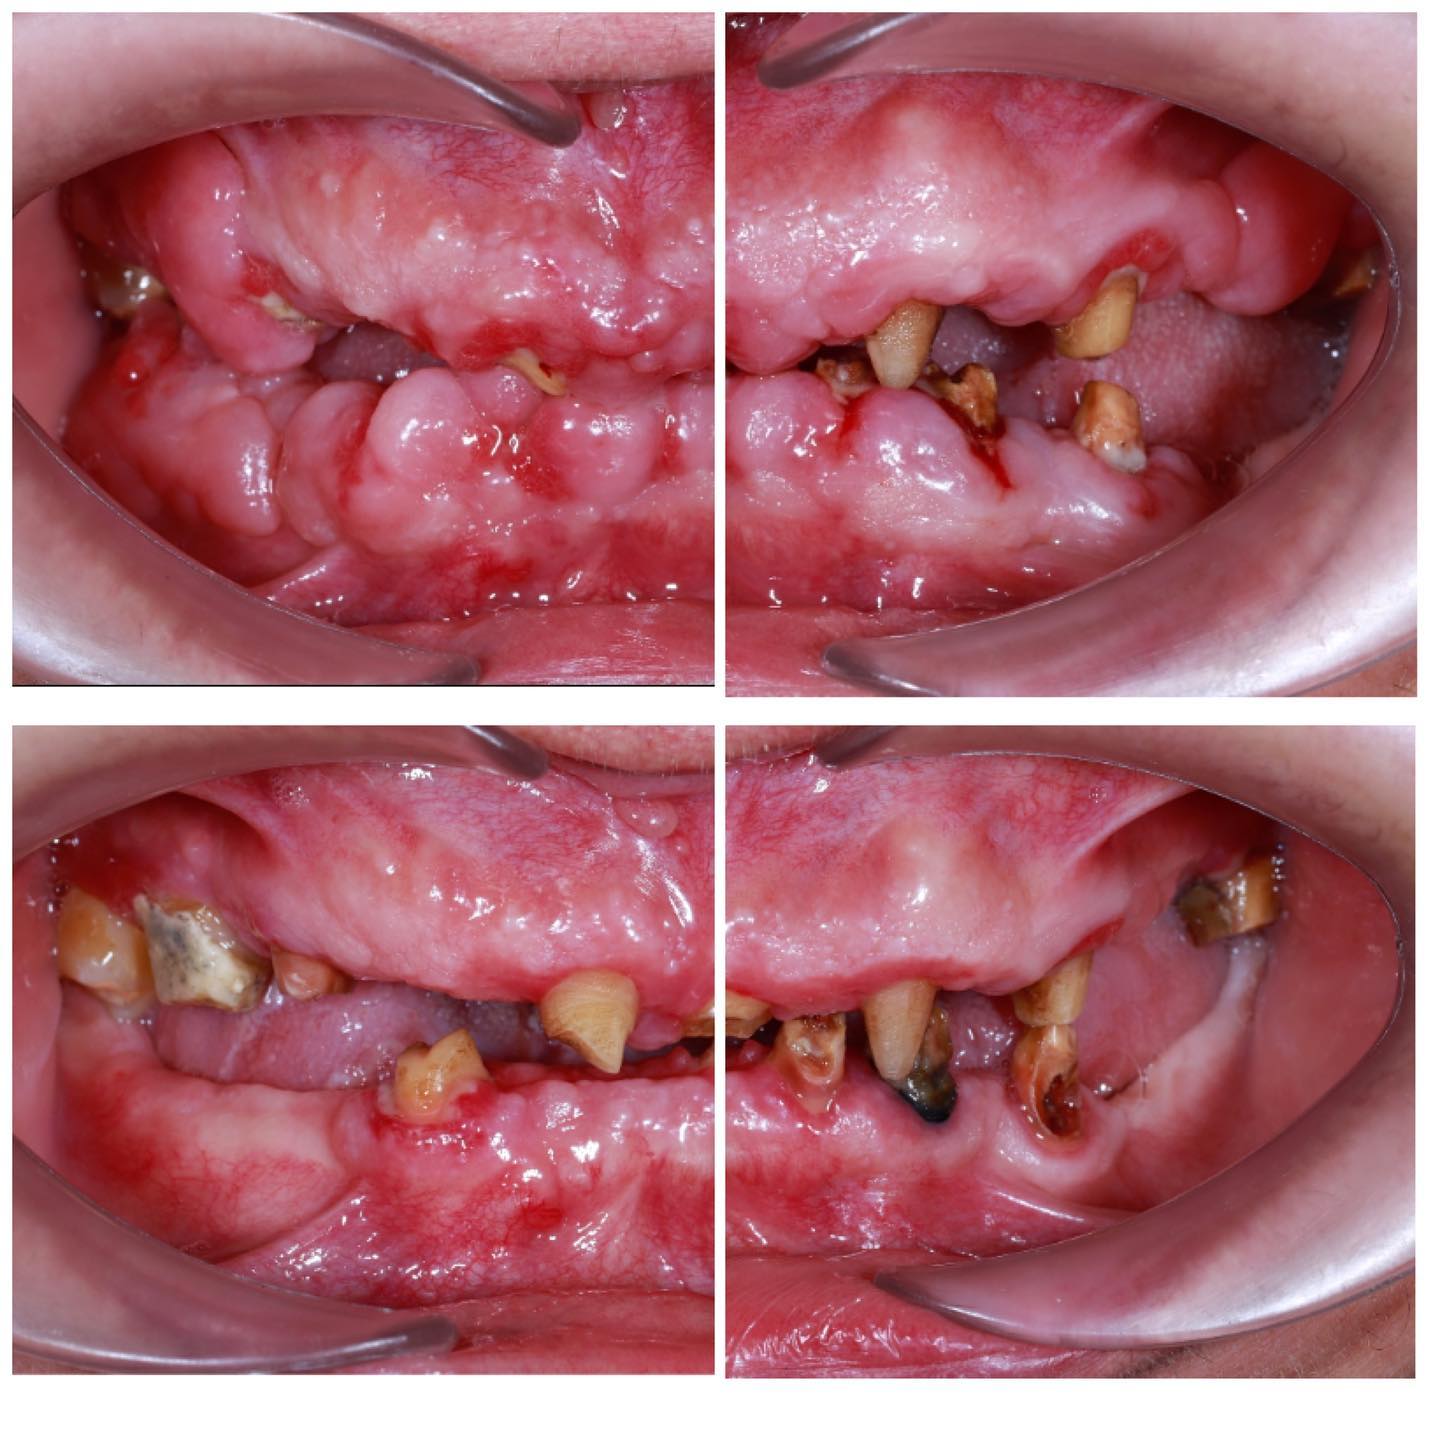

Diş ətinin iltihabı

Diş ətində olan qızartı, şişkinlik və qanama kimi əlamətləri olan diş əti xəstəlikləri müalicə olunmalı və sonra qapaq ilə implant edilməlidi